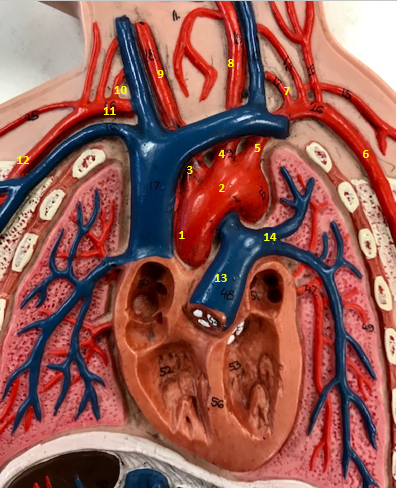

Aorta

Name #2

Brings blood out of left ventricle

Function of aorta

Brachiocephalic artery

Name #3

Supplies oxygenated blood to right arm shoulder neck and head

Function of brachiocephalic artery

Left common carotid artery

Name #4

Supplies oxygenated blood to left neck and head

Function of left common carotid artery

Left subclavian artery

Name #5

Supplies oxygenated blood to left arm shoulder

Function of left subclavian artery

Left axillery artery

Name #6

supplies blood to left armpit and upper limb

Function left axillary artery (6)

Left vertebral artery

Name #7

Supplies blood to brain and spinal cord

Function of left vertebral artery (7)

Left common carotid artery

Name #8

Supplies blood to left neck and head

Function of left common carotid artery (8)

Right common carotid artery

Name #9

Supplies oxygenated blood to right neck and head

Function of right common carotid artery (9)

Right vertebral artery

Name #10

Supplies blood to brain and spinal cord

Function of right vertebral artery (10)

Right subclavian artery

Name #11

Supplies blood to right arm and shoulder

Function of right subclavian artery

Right axillery artery

Name #12

Supplies blood to right armpit and upper limb

Function of right axillery artery (12)

Pulmonary trunk

Name #13

Bring blood out of right ventricle to lungs

Function of pulmonary trunk (13)

Left pulmonary artery

Name #14

Bring blood to left lung

Function of left pulmonary artery (14)